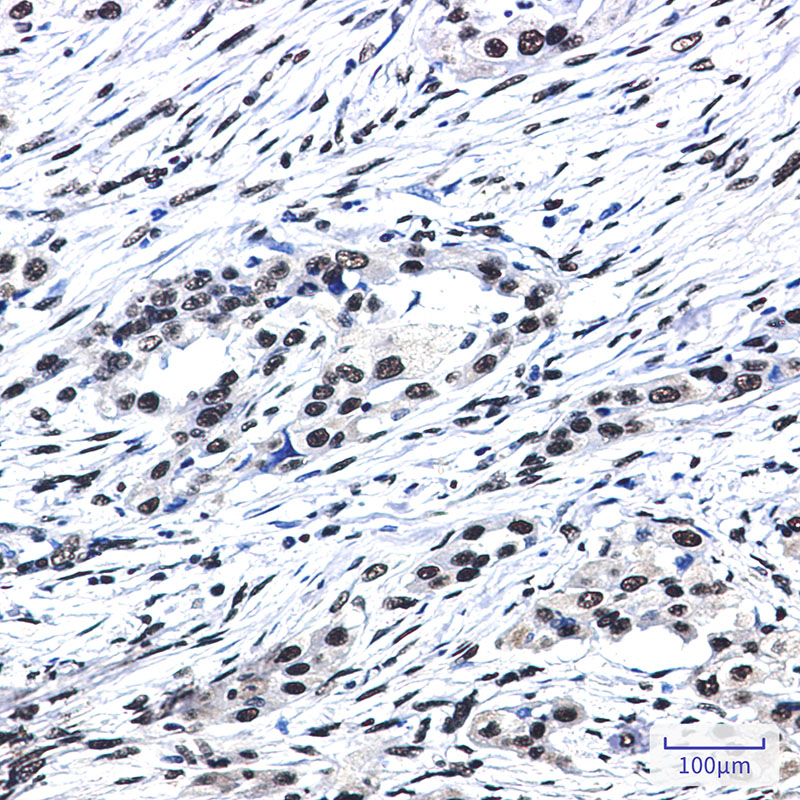

- Immunohistochemistry analysis of paraffin-embedded Human lung cancer using SF3B1 antibody.High-pressure and temperature Sodium Citrate pH 6.0 was used for antigen retrieval.